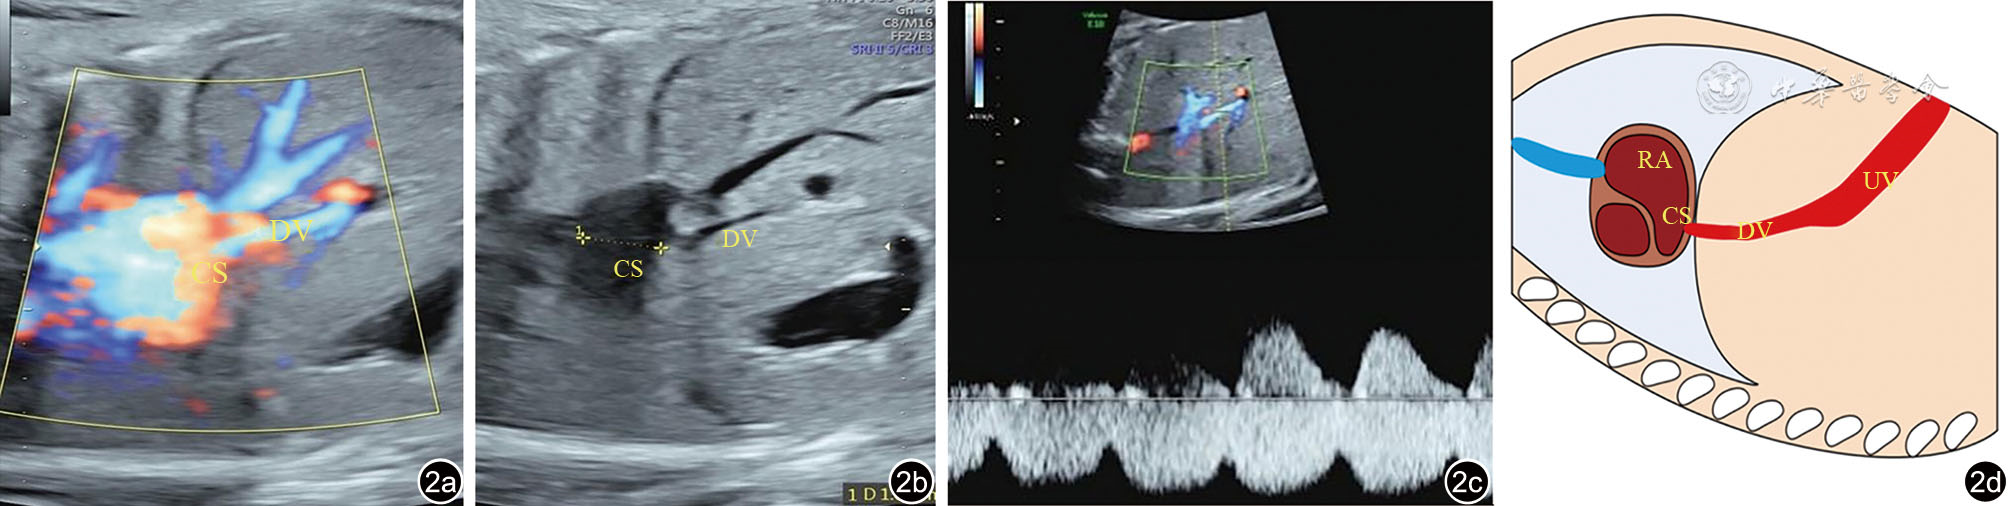

图2 静脉导管异常汇入冠状静脉窦超声图像及示意图。图a、b为肋下视图显示静脉导管外观正常,静脉导管连接到扩张的冠状静脉窦中;图c为静脉导管可见正常的特征性三相血流;图d为静脉导管异常汇入冠状静脉窦示意图 注:CS为冠状静脉窦;DV为静脉导管;RA为右心房;UV为脐静脉